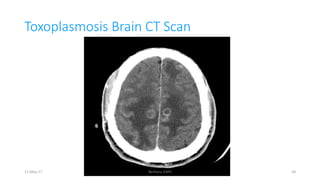

Toxoplasmosis Brain CT Scan

CNS Toxoplasmosis – Dx & dDx

Diagnosis - MRI - multiple lesions - in some cases only a

single lesion is seen.

 Pathologically - inflammation and central necrosis and, as a

result, demonstrate ring enhancement on contrast MRI or on

double-dose contrast CT.

 There is usually evidence of surrounding edema.